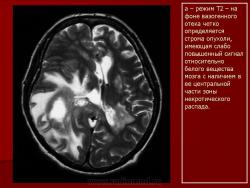

Лимфомы головного мозга.